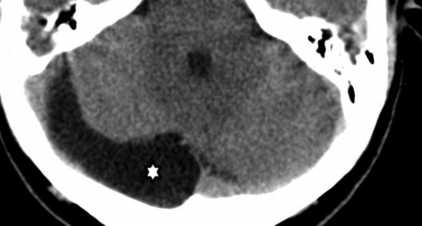

Son cavidades extra-axiales que contienen LCR y no comunican con el sistema ventricular.3,4,5,8,15 En los neonatos se los puede diagnosticar mediante ecografía transfontanelar.15 En imágenes presentan las características habituales de un quiste simple (►Fig. 12).3,5,15 El diagnóstico diferencial debe realizarse con:3,4,5,15

TC de cerebro en la que se señala la presencia de un quiste aracnoideo de la fosa posterior con prolongación parasagital derecha (*).